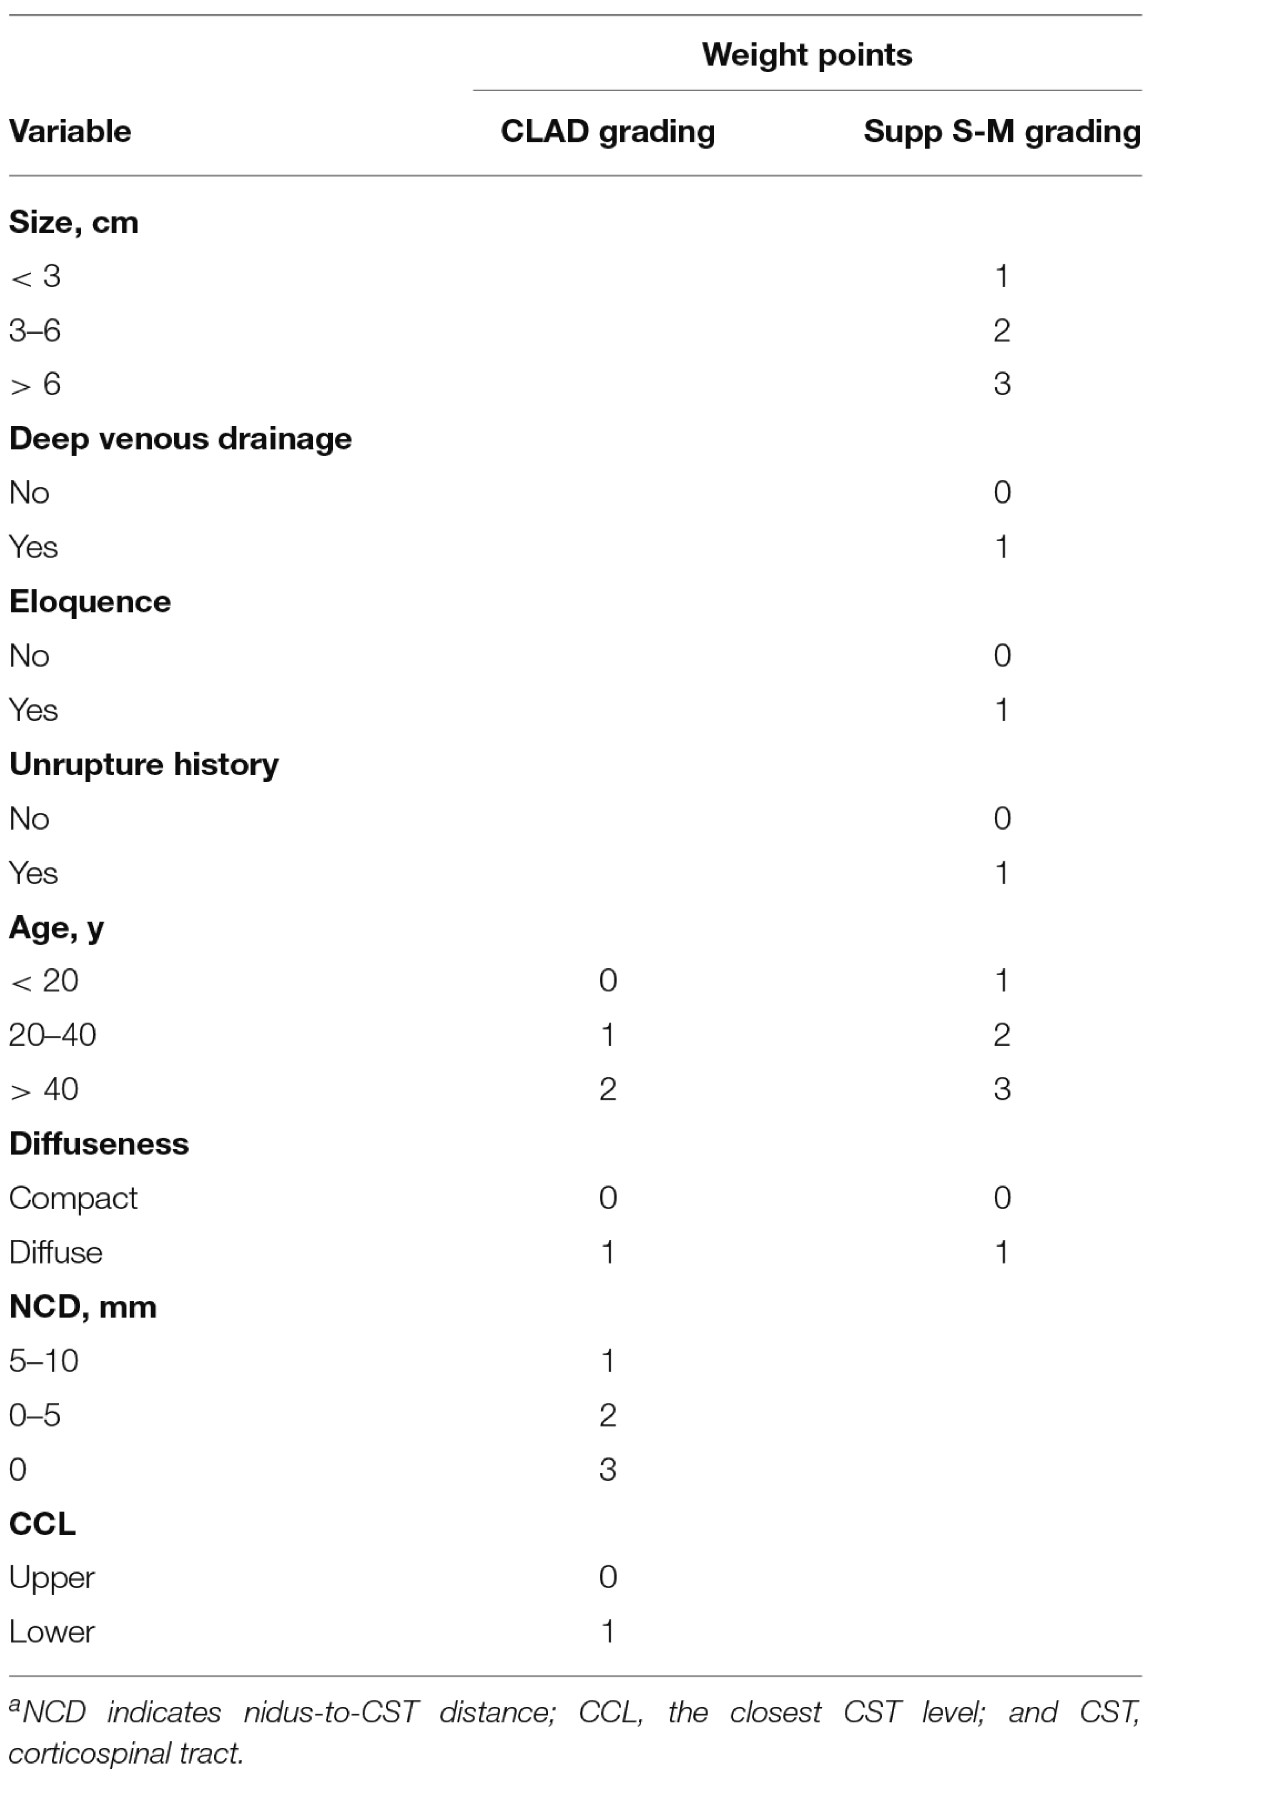

该研究纳入2013年1月至2018年6月期间90例手术治疗的脑AVM患者,畸形团与CST的最短距离小于10mm。所有患者在手术前两周内进行3.0T MRI成像,包括DTI和3D TOF MRA以及DSA造影,并进行MRA三维重建。主要研究指标为术前、术后7天及最后一次电话随访时患者的肌力情况;依据医学研究委员会量表(MRCS评分)进行0-5级肌力评分。术后对侧肢体肌力MRCS评分降低定为医源性肌力减退;永久性肢体肌力减退定为运动功能预后差。研究结果指标,包括畸形血管团至CST的距离(nidus-to-CST distance,NCD)、最接近CST水平(closest CST level,CCL)、深穿支动脉供血、弥漫型AVM以及Spetzler-Martin分级系统的补充指标,包括畸形血管团大小、是否位于功能区、是否深部静脉引流以及畸形团破裂史。通过不同的多因素logistic回归分析制定三种模型,选择预测性最强的模型建立评分系统,并通过ROC分析来验证评分系统的预测准确度。

90例AVM患者中,男性49例(54.4%),女性41例(45.6%);平均年龄27.2±13.1岁。其中9例(10%)入院时已有运动功能障碍。术后第7天41例(45.6%)对侧肢体肌力减退。随访6-69个月,平均2.7±1.5年;无患者死亡。最后随访时,21例(23.3%)永久性对侧肢体肌力减退。Logistic回归分析显示,NCD(P=0.001)、CCL(P=0.017)、患者年龄(P=0.004)以及弥漫性AVM(P=0.021)是术后运动功能预后差的独立危险因素。作者根据上述危险因素的权重,制定包括畸形血管团至CST紧密距离的分级系统(CLAD量表分级)(表1)。CLAD量表总分0-7分,截止阈值分值为3.5分。根据该量表可将近皮质脊髓束AVM分为两组:①CLAD量表分级1-3分的低危组,术后永久性肢体运动功能障碍发生率为0%–7.1%;②CLAD量表分级4-7分的高危组,术后永久性肢体运动功能障碍发生率为33.3%–66.7%。

表1. CLAD分级量表和supp S-D分级量表。